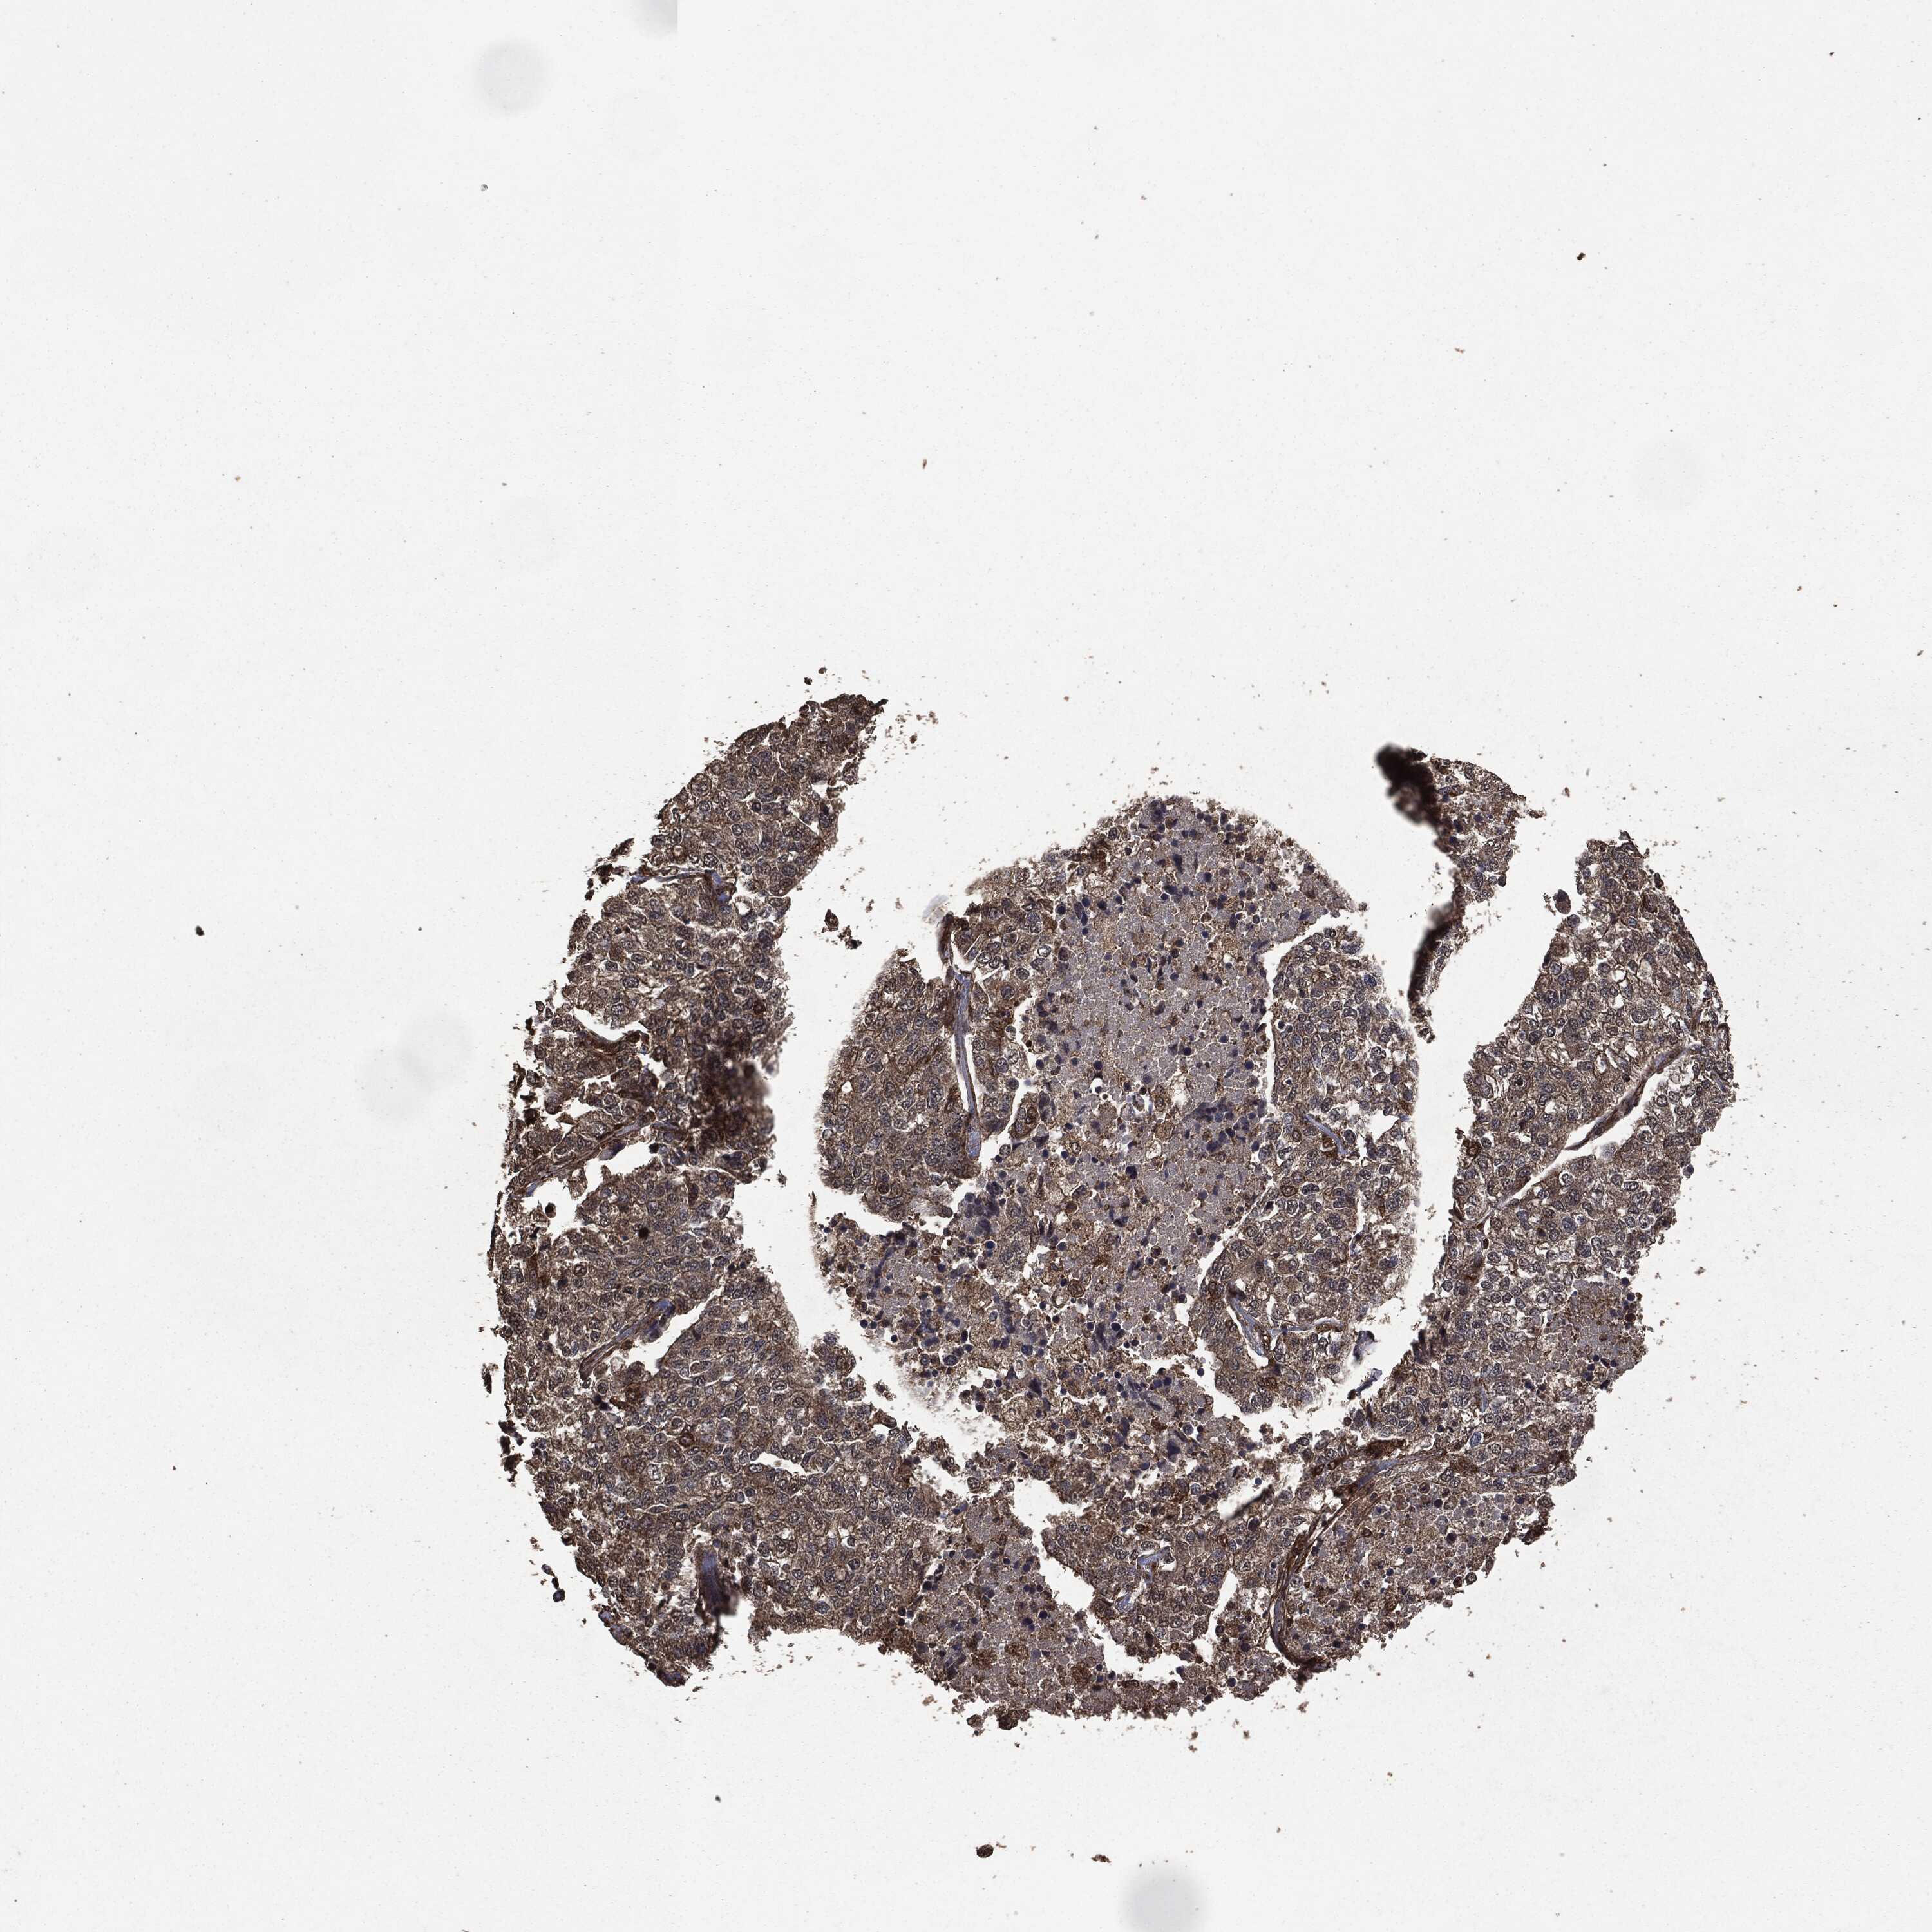

CANCER LUNG CANCER Show tissue menu

LUAD TCGA LUAD VALIDATION LUSC TCGA LUSC VALIDATION PROTEIN LUAD CPTAC PROTEIN LUSC CPTAC PROTEIN EXPRESSION